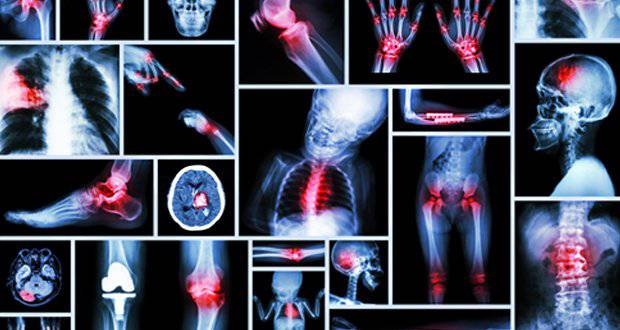

La posturologie s’applique pour des douleurs fonctionnelles avant qu’elles ne deviennent des troubles organiques, mécaniques :

Podalgies (métatarsalgies, névrome de Morton, Hallux valgus ou Rigidus, aponévrosite plantaire)Talalgies (épine calcanéenne, enthésopathies, tendinites d’Achille…)

Gonalgies (syndrome rotulien, syndrome de l’essuie-glace…)

Lombalgies (lumbago, douleurs sacro-iliaque…)

Cervicalgies

Céphalées de tensions